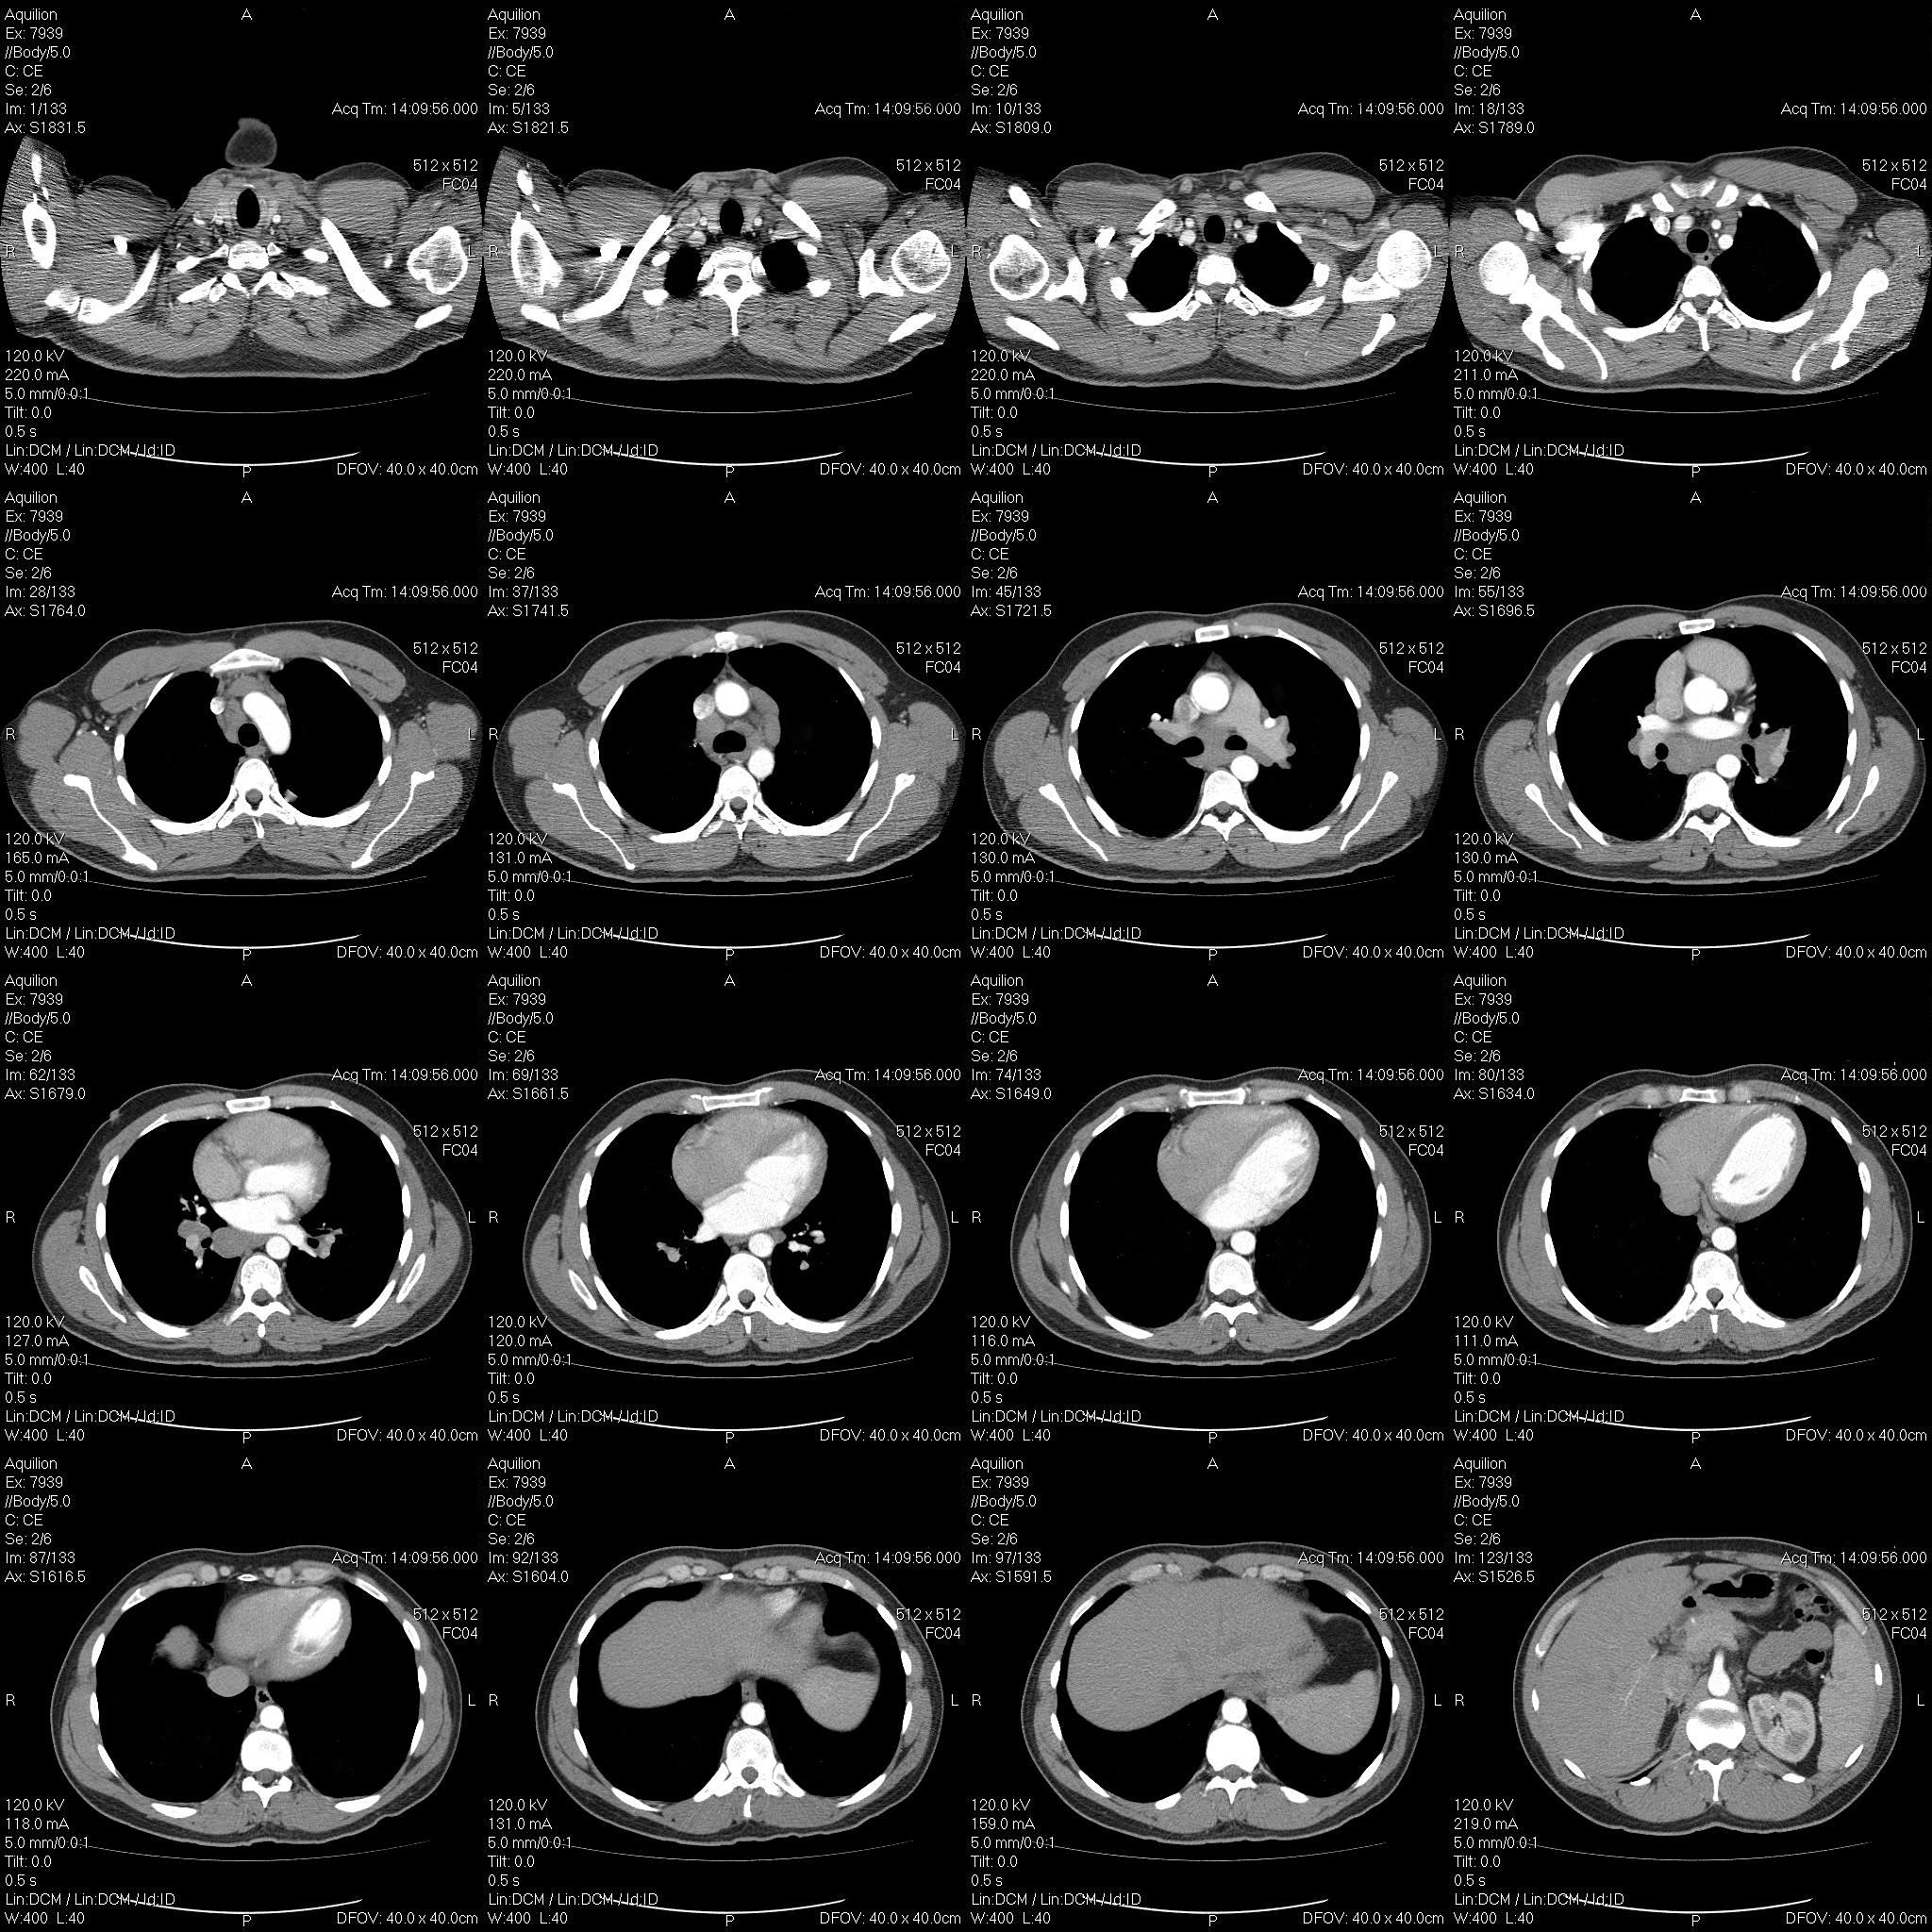

CT扫描在诊断和评估结节性甲状腺肿中的价值

结节性甲状腺肿,即甲状腺内出现结节,通常是良性的。CT扫描作为一种影像学检查手段,在评估结节性甲状腺肿方面发挥着重要作用。

1. 诊断和定位: CT扫描能够清晰地显示甲状腺结节的存在、大小、形状、数量以及与周围组织的关系,帮助医生精确定位结节。

2. 鉴别诊断: CT扫描可以帮助区分结节性甲状腺肿与其他甲状腺疾病,例如甲状腺癌或甲状腺炎。通过观察结节的钙化、囊变、边界清晰度等特征,CT扫描可以提供更准确的诊断信息,辅助医生进行鉴别。

3. 指导治疗方案: CT扫描结果可以为结节性甲状腺肿的治疗提供重要依据。例如,在进行甲状腺结节穿刺活检时,医生可以根据CT图像确定最佳穿刺路径,提高穿刺的准确性和安全性。对于需要手术治疗的患者,CT扫描可以帮助医生评估结节的大小、位置以及与周围器官的关系,从而制定更安全、有效的手术方案。

4. 随访评估: 对于已经确诊为结节性甲状腺肿的患者,CT扫描可以用于动态监测结节的变化。通过比较不同时间点的CT图像,医生可以观察结节的生长速度、变化趋势以及是否存在恶变迹象,从而及时调整治疗方案和随访计划。